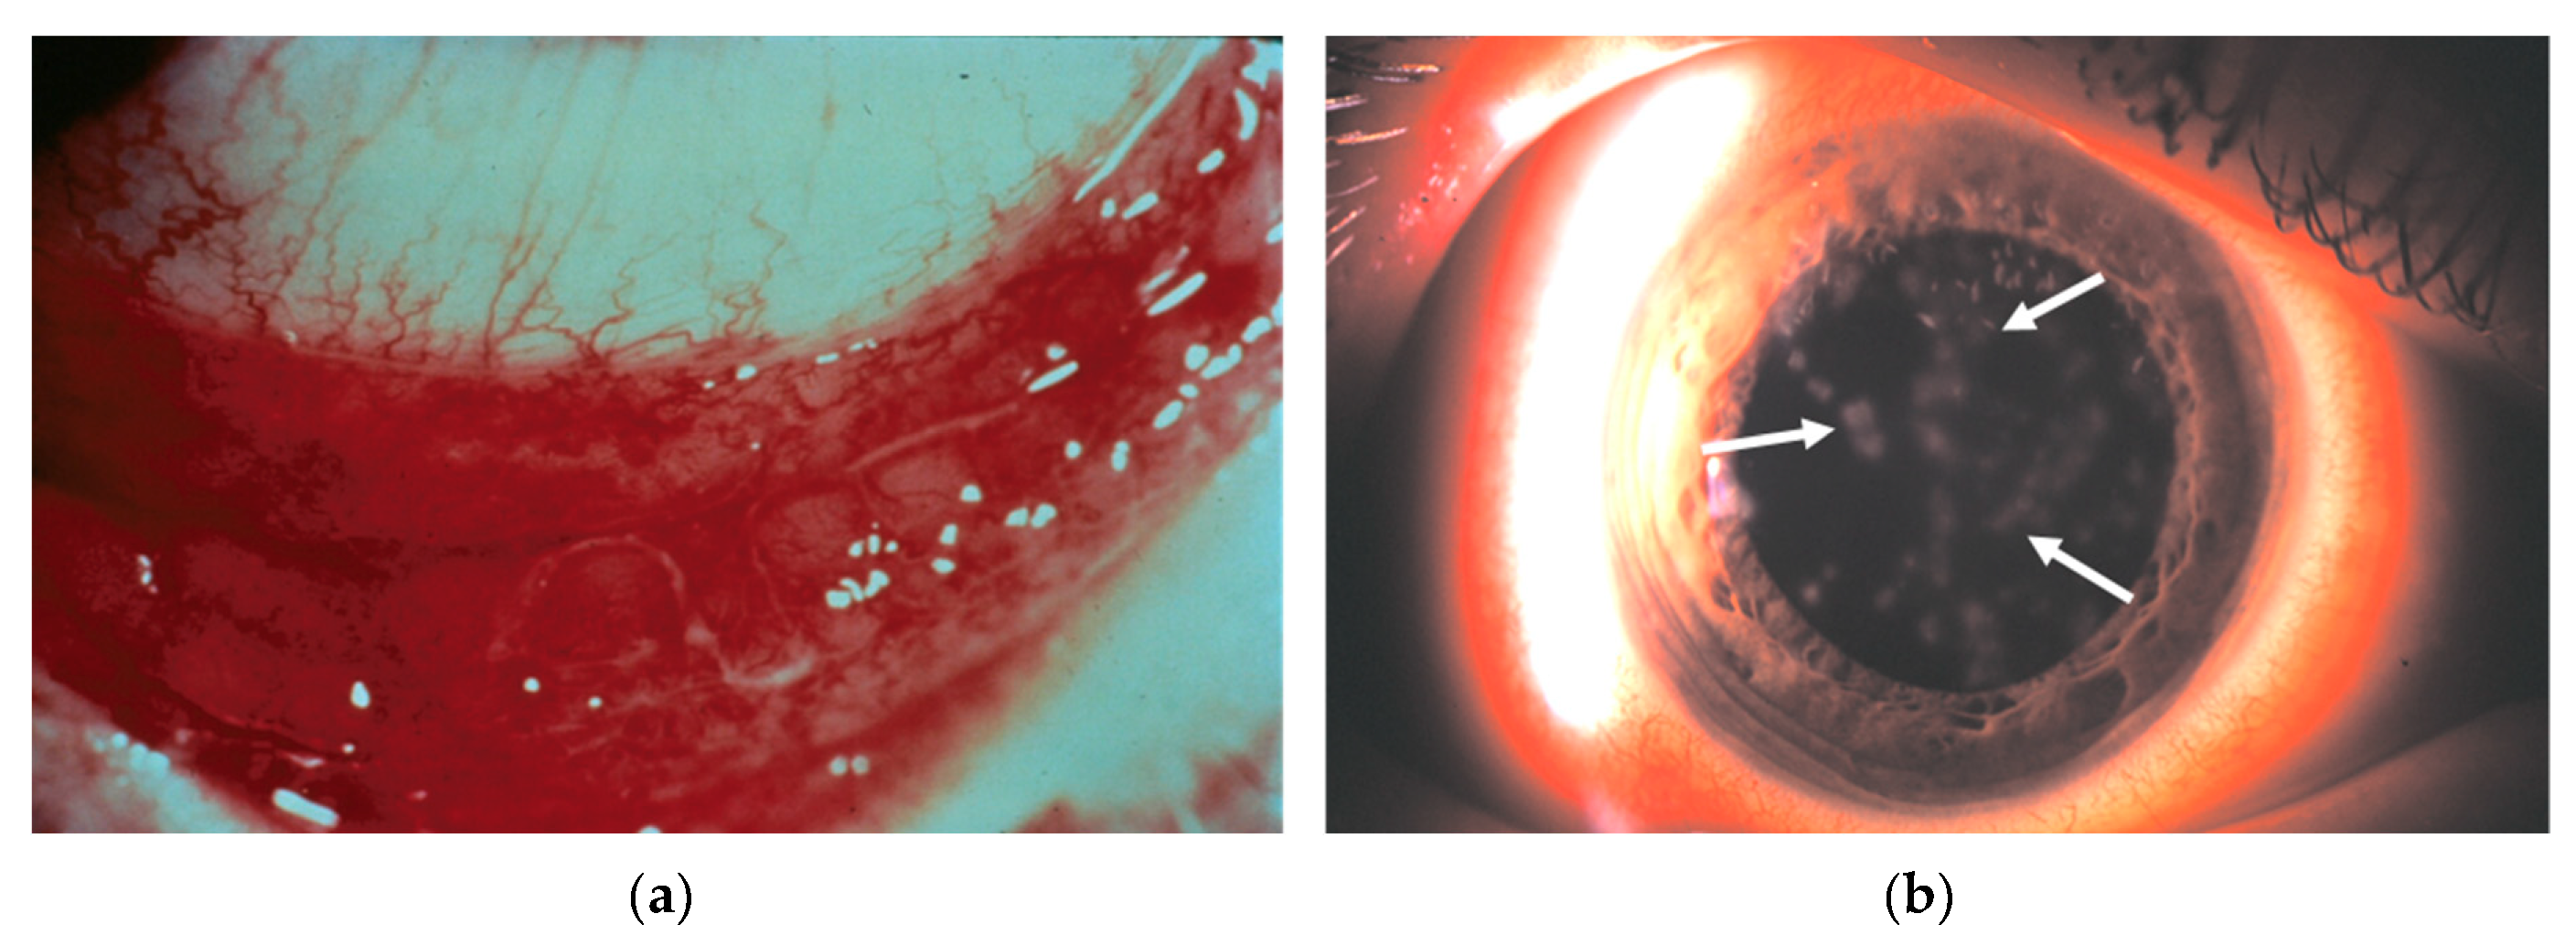

- Chintakuntlawar, A.V.; Chodosh, J. Cellular and tissue architecture of conjunctival membranes in epidemic keratoconjunctivitis. Ocul. Immunol. Inflamm. 2010, 18, 341–345. [Google Scholar] [CrossRef] [PubMed]